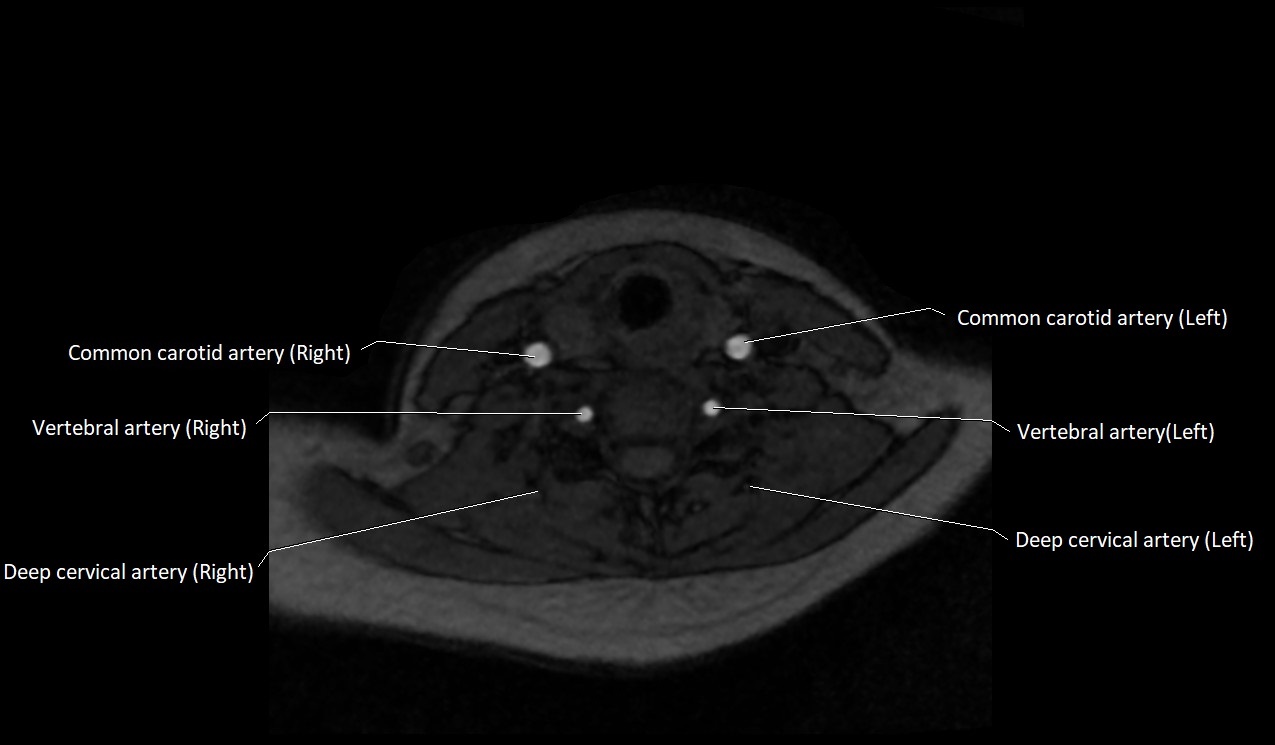

MRI Appearance:

• T1-Weighted Images:

• Appears as a tubular, hypointense (dark) structure relative to muscle

• May show flow void if the blood flow is fast

• T2-Weighted Images:

• Typically hypointense or isointense to muscle, but can be hyperintense if slow flow or stasis is present

MRI images

image